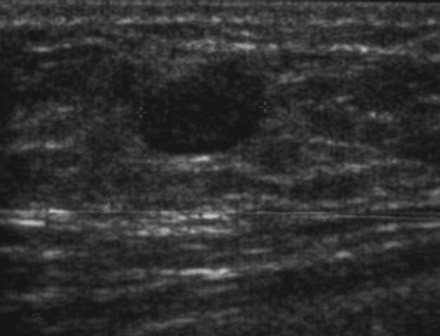

The target dataset was developed from 35 breast ultrasound scans that were segmented by an image-processing expert with extensive experience in breast lesion segmentation (the second author). The images, collected from the Web, are of different dimensions, ranging from to pixels (Figure 3, images resized for sake of illustration). These are the same images used to introduce EFIS originally [1].

Ultrasound images are generally difficult to segment, primarily due to the presence of speckle noise and low level of local contrast. It should be noted that the segmentation of ultrasound actually does require a complete processing chain, (including proper preprocessing and post-processing steps). However, the purpose of using these images was solely to demonstrate that the accuracy of the segmentation can be increased with the application of SC-EFIS.